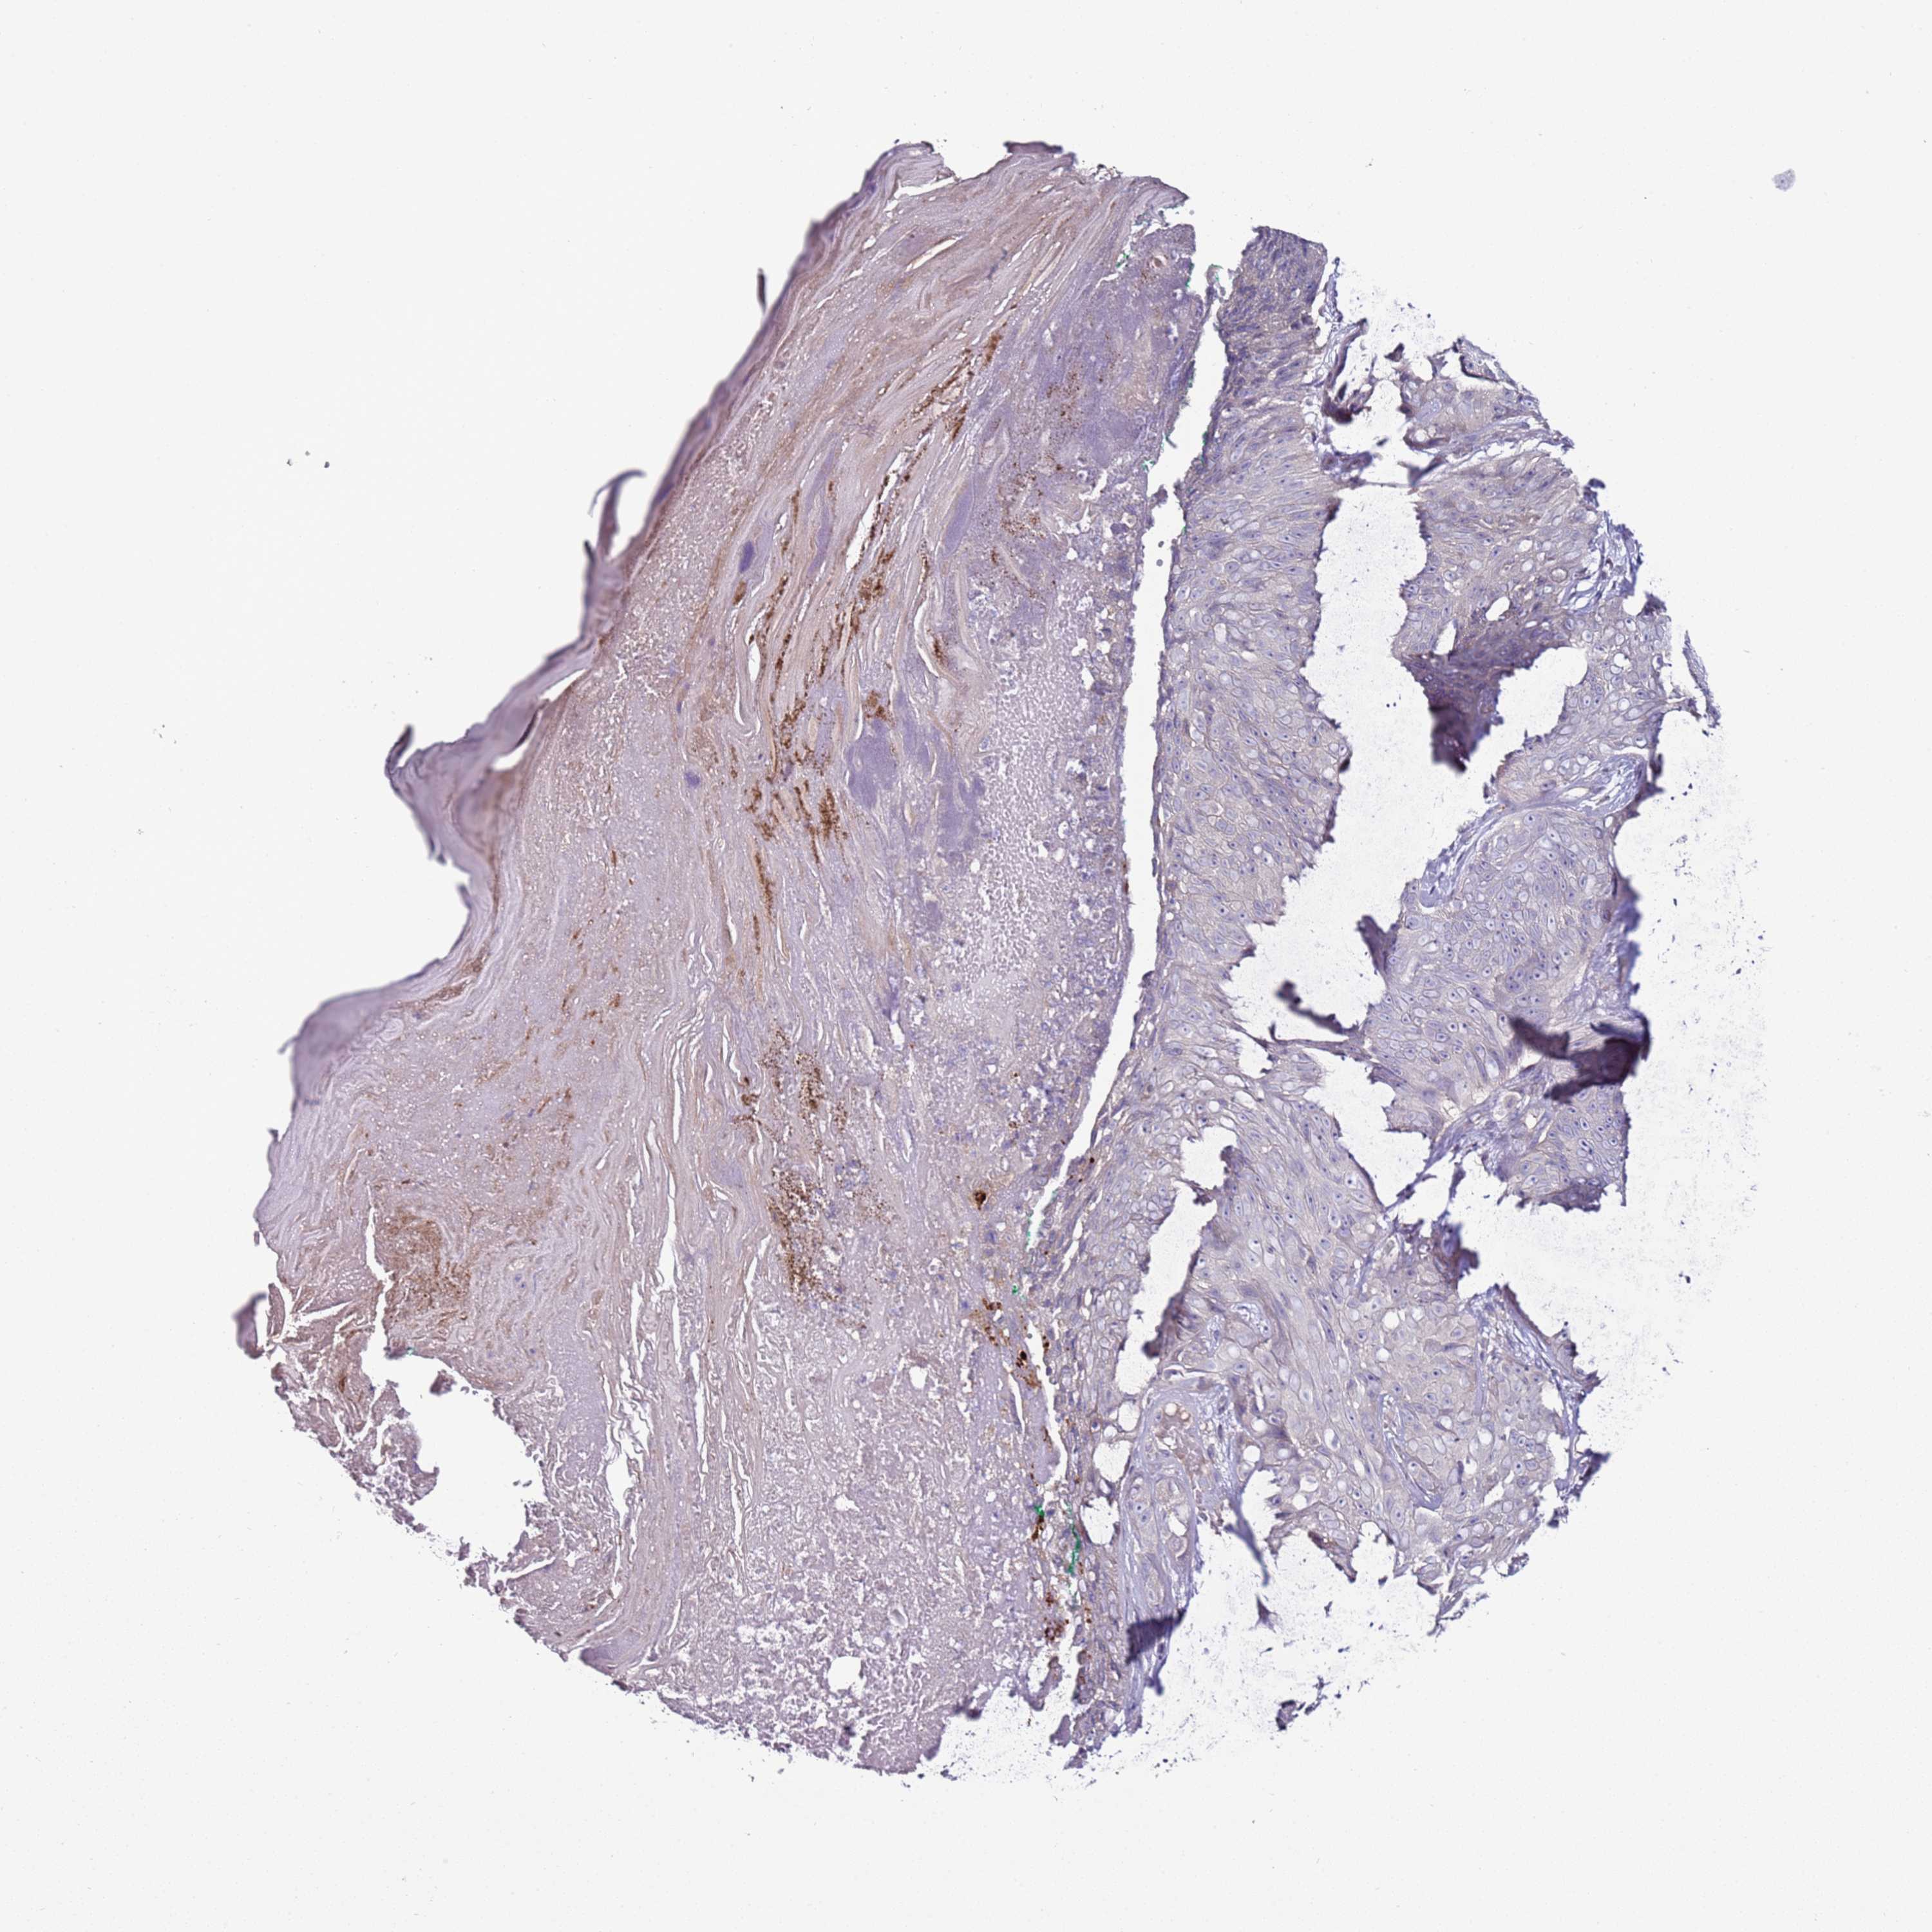

SKIN CANCER - Protein expressioni

A mouse-over function shows sample information and annotation data. Click on an image to view it in a full screen mode. Samples can be filtered based on level of antibody staining by selecting one or several of the following categories: high, medium, low and not detected. The assay and annotation is described here.

Each image is clickable and will lead to virtual microscopy that enables deeper exploration of all samples and also displays staining intensity scores, fraction scores and subcellular localization as well as patient and tissue information for each sample.

Antibody HPA039764

Staining

High

Intensity

Strong

Quantity

>75%

Location

Nuclear

Basal cell carcinoma

Squamous cell carcinoma, NOS

Squamous cell carcinoma, metastatic, NOS

Squamous cell carcinoma in situ, NOS